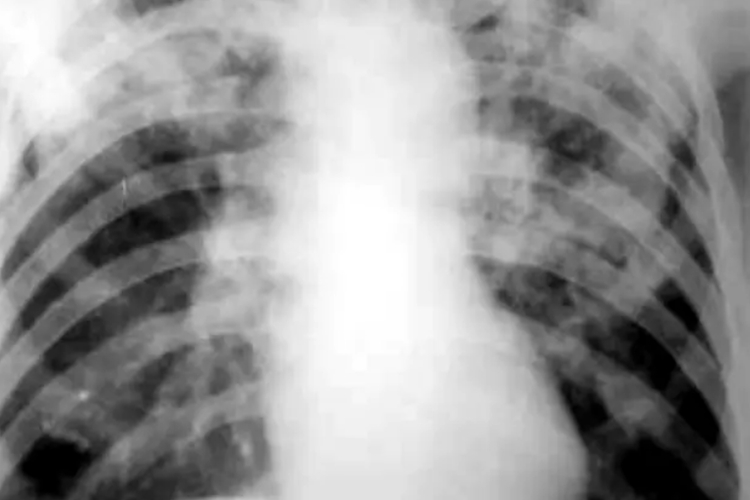

亚急性血行播散型肺结核:表现为双肺上、中野粟粒状或较粟粒更大的小结节影,大小不一、密度不等分布不均,即“三不均匀”。肺尖部及锁骨下病灶可为硬结、钙化及纤维化,其余病灶呈增殖或渗出性改变。